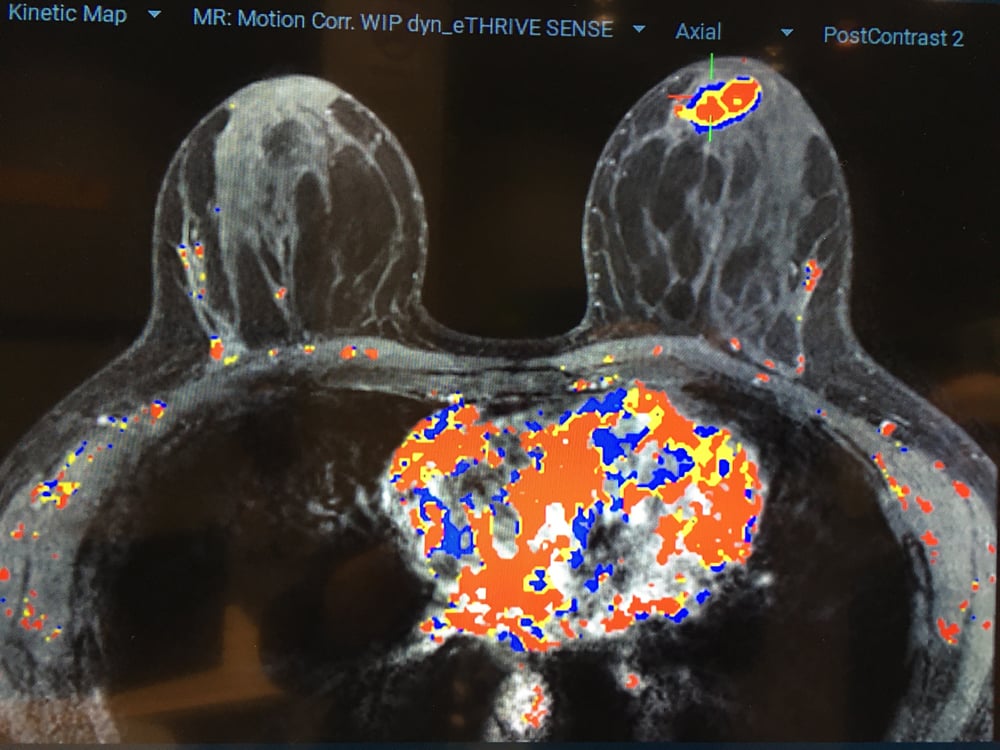

Here are images of some of the newest new medical imaging technologies displayed on the expo floor at the Radiological Society of North America (RSNA) 2019 meeting. Use the slider images below to see the photos.